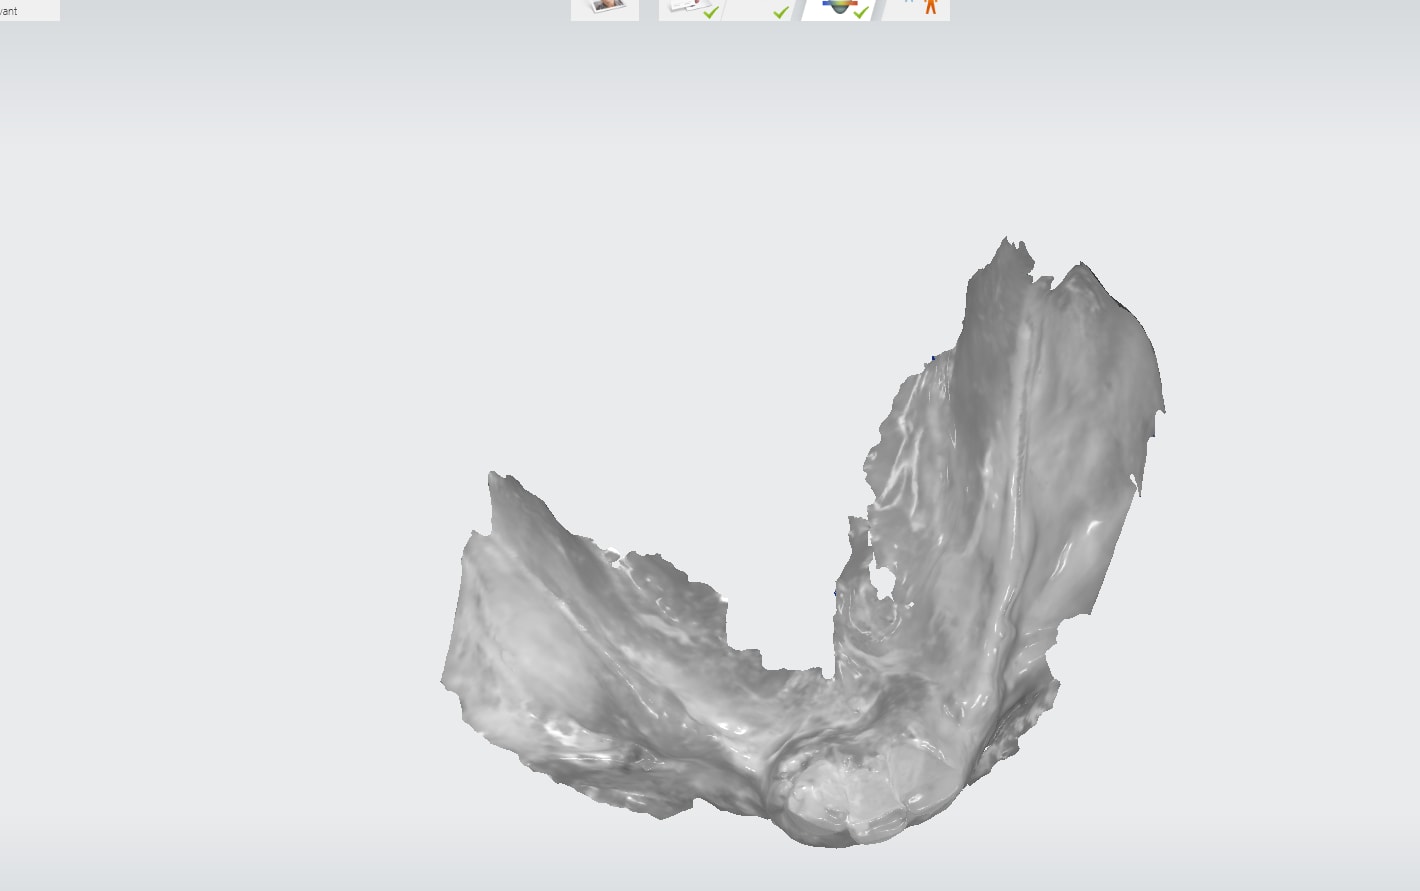

Bon petit cas de ce matin. Reprise de traitement endo sur 17, Préparation coronoradiculaire infragingivale.

Retraction gingivale et empeinte optique. Bonne lisibilité des limites dans l'empreinte optique mais j'ai fais un silicone pour tester la fonction qui a très bien marché.

On s'éclate! https://www.meditlink.com/webViewer?shareKey=f58f58e8-4d35-4a29-b8f8-82b6dccf92b7

Sinon Kingsu, superbe ton sauvetage de 17.